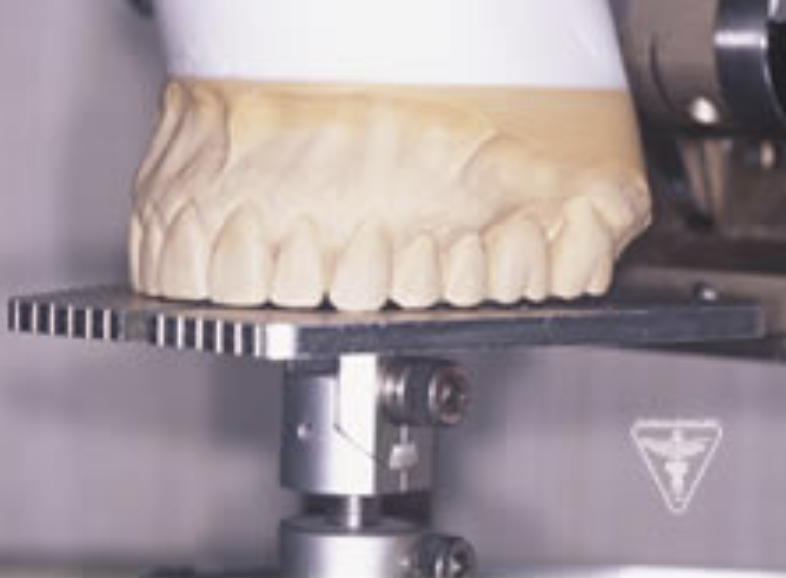

治療後

かみ合わせの深さを改善し、左下の骨を作り人工歯根で再構築しました。

前歯は、患者さんの希望でフルセラミックで対応しました。